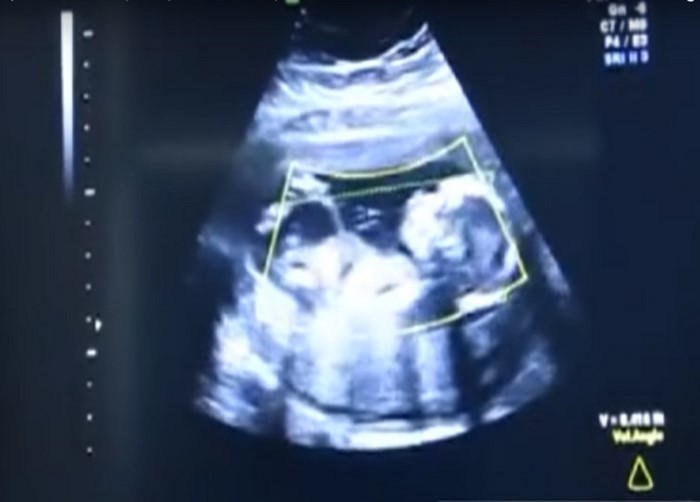

¡A sus 41 semanas de embarazo, la mujer descubrió que su hijita no estaba alojada en su útero, como debería ser, sino en el abdomen! Cuando los médicos se dieron cuenta de esta compleja anomalía, sin pérdida de tiempo, enviaron a la futura madre al salón. ¡Cualquier retraso podría terminar en tragedia!

Ahora, los médicos dicen que la causa del incidente podría ser una anomalía congénita singular del útero de la mujer. El embrión, es probable que haya atravesado una fisura del útero, para luego implantarse en la cavidad abdominal.